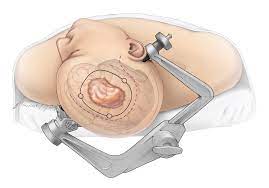

Overview

Package includes:

Days in hospital : 3 to 4 Days (For patient and one attendant)

Days in hotel : 15 Days (For patient and one attendant)

Room type in hospital : Shared

Room type in hotel : Private

Hotel category: Standard

Value added benefits of the Herniorrhaphy - Inguinal - Unilateral:

Ø Doctor consultation charges

Ø Lab tests and diagnostic charges

Ø Room charges inside hospital during the procedure

Ø Surgeon Fee

Ø Nursing charges

Ø Hospital surgery suite charges

Ø Anesthesia charges

Ø Routine medicines and routine consumables (bandages, dressings etc.)

Ø Food and Beverages inside hospital stay for patient and one attendant.